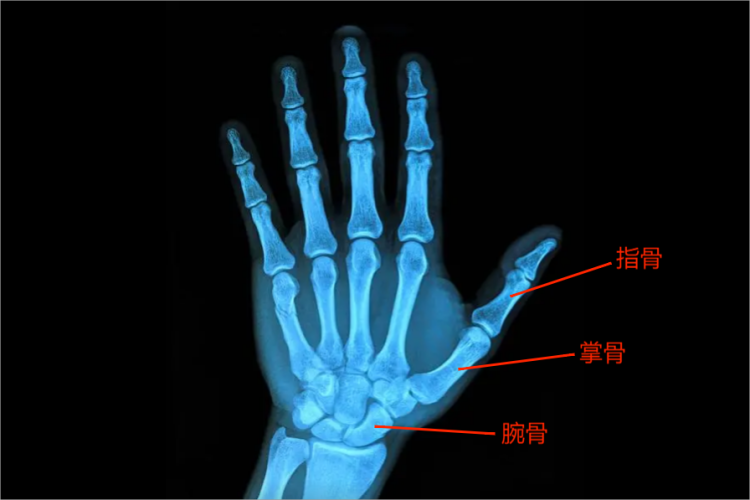

左手CT可见手部骨骼的结构,可分为腕骨、掌骨和指骨,手部是常用且较为灵活的关节,临床上容易受到暴力损伤。

左手CT可见左手骨骼的结构,即腕骨、掌骨和指骨,腕骨可见8块,掌骨可见5块,指骨可见14块。在CT上骨皮质表现为致密线状或带状影,骨小梁为细密网状影,干骺端表现为骨小梁交错构成细密的网状影,密度低于骨皮质,网格间为低密度的骨髓组织。